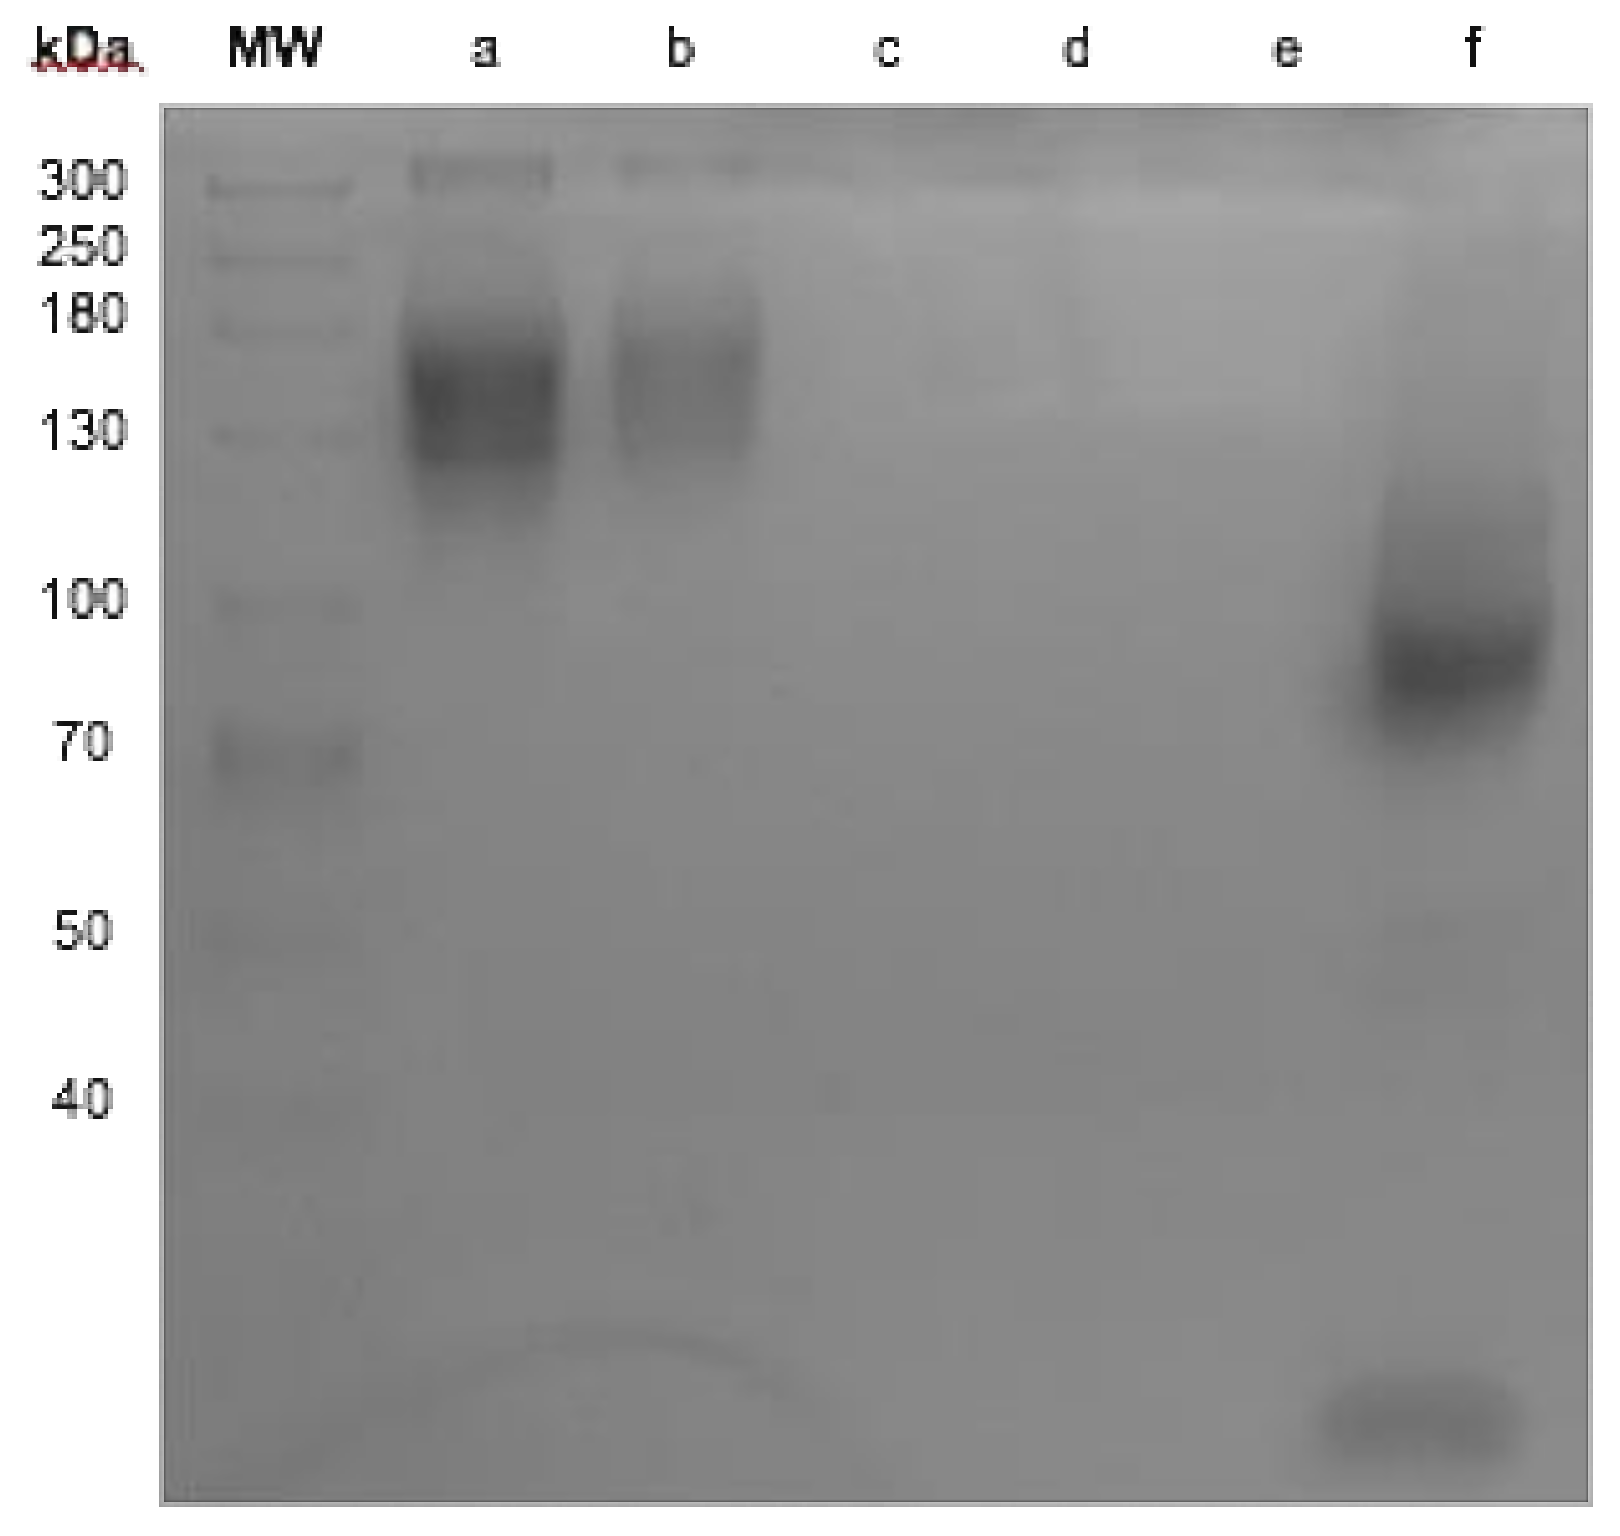

2.2. Antibody Integrity

4.5. Radiolabeling